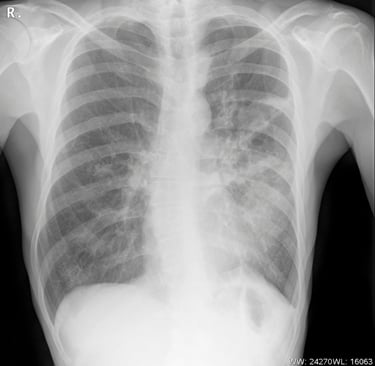

Dr. Memet Işık Notu: Skolyoz teşhisinde altın standart fiziksel muayene ve "Skolyoz Grafisi" adı verilen boydan boya çekilen röntgenlerdir. Bu sayede "Cobb Açısı" ölçülerek tedavi haritası çıkarılır.